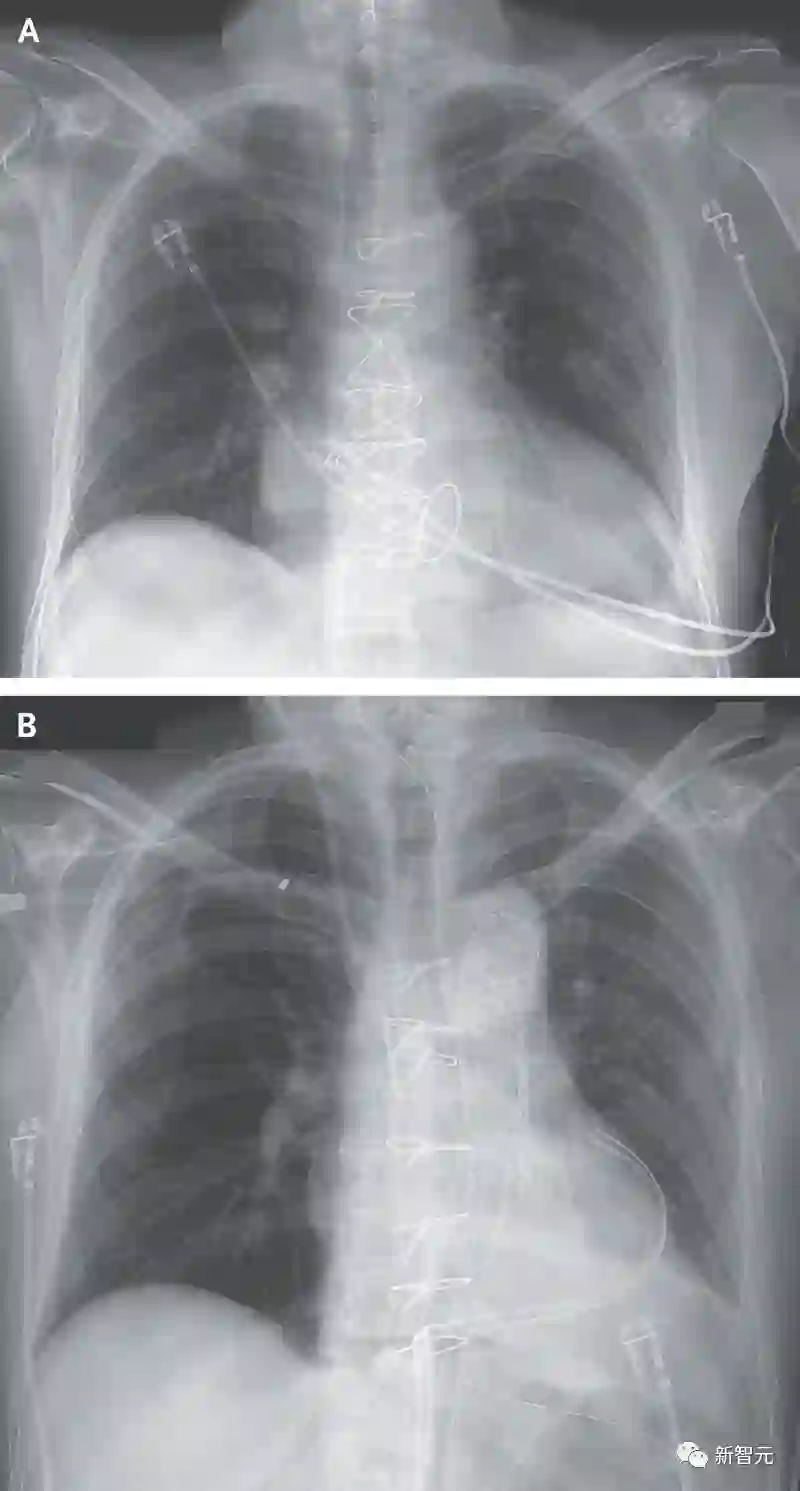

移植手术完成后,Kelly只能依靠呼吸机来维持体征,同时研究人员对其进行了为期3天的测试。

因此,术后医生对两位受试者进行了72小时的心脏功能监测。

在两个器官中均未观察到早期排斥的迹象,并且无需额外的机械或药物便能维持心脏功能。